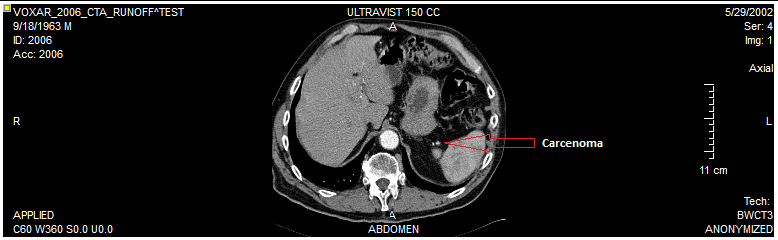

The Annotation tool can be used to create annotations on various points in the image which might be interesting to the viewer for any reason. To do so, click the Annotation button on the tool bar and enter a value in the annotation bar.

Then elect a point in the image and click to create annotation in the image.

The annotations will be saved on the side with a line directing to the point in the image which the annotation belongs to. You can then capture the image with annotations and create a separate series if desired. To erase the annotation, right click on the image and select Delete. You can also choose to edit the annotation text with the right-click menu.